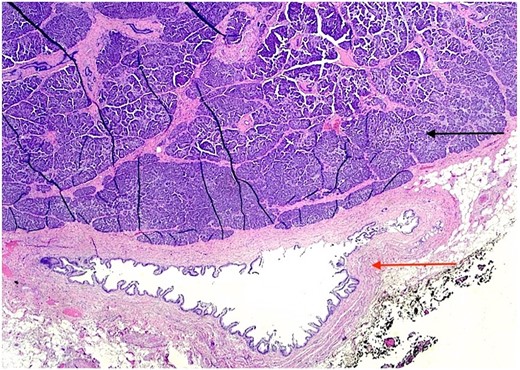

The patient underwent an elective laparoscopic cholecystectomy. During the surgery, findings were consistent with chronic cholecystitis. No abnormalities were visible upon gross inspection. Postoperatively, the patient recovered well and was discharged on the same day. The macroscopic histopathological examination revealed an intact GB with pink serosa. The mucosa was yellow-red without focal lesions. The microscopy showed chronic cholecystitis and the presence of a 1 cm focal nodule in the GB wall compatible with ectopic pancreatic parenchyma containing only acinar and ductal components (Figs 2–3). There was no evidence of dysplasia or malignant transformation in the analyzed sections. Since no malignancy was found among the EPT, there was no need for further treatment.

H & E stain 20×: Ectopic pancreatic parenchyma, composed of ductal and acinar components (black arrow).

H & E stain 20×: Ectopic pancreatic parenchyma (black arrow), present in the gallbladder wall, composed of mucosa with underlying muscularis and adventitia (red arrow).